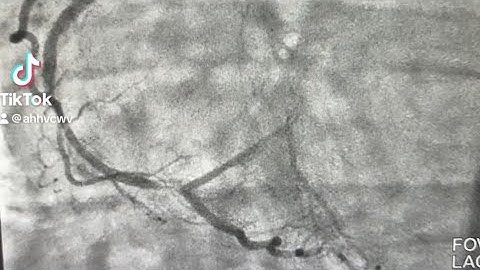

An OCT guided PCI to solve a non-optmized provisional technique - Dr Cristina Aurigemma